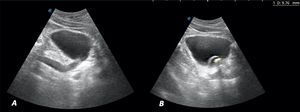

Ante el cuadro sugestivo de cólico renoureteral derecho, se decide realizar ecografía a pie de cama en consulta con los siguientes hallazgos: riñón derecho con dilatación de la vía excretora sugerente de hidronefrosis grado II/IV (figs. 1A y B). Vejiga bien replecionada con imagen anecoica tubular en el corte longitudinal que corresponde al uréter distal dilatado (fig. 2A). En el interior de la vejiga se observa imagen anecoica con borde hiperecoico bien definido que sugiere ureterocele y en su interior, una imagen hiperecoica con sombra acústica posterior de 9,76mm compatible con litiasis (fig. 2B). Riñón izquierdo (fig. 1C), hígado, vesícula y vía biliar intra y extrahepática, bazo, zona pancreática y próstata sin alteraciones.

A) Corte longitudinal. Imagen anecoica a la entrada de la vejiga, que corresponde al uréter dilatado. B) Corte longitudinal. Vejiga bien replecionada con imagen anecoica, con borde hiperecoico bien definido (imagen quística) que sugiere ureterocele. En su interior imagen hiperecoica con sombra acústica posterior de 9,76mm compatible con litiasis.